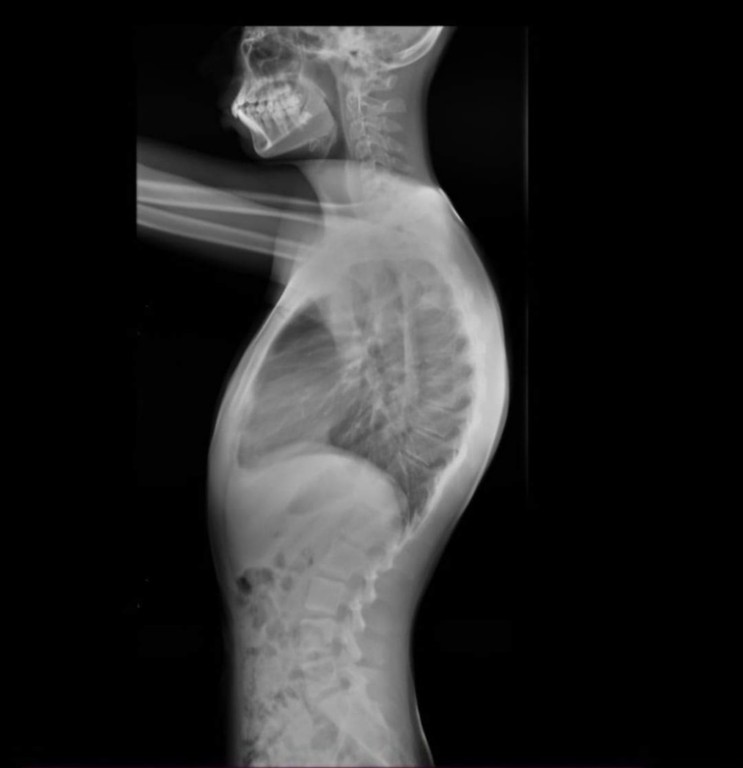

تقوس الظهر المفرط هو حالة طبية تتميز بانحناء غير طبيعي في الجزء العلوي من العمود الفقري. على عكس الانحناءات الطبيعية للعمود الفقري، يؤثر الحداب المفرط على المظهر والوظيفة. تعمل أحزمه تقوس الظهر PioBrace-KT على تصحيح هذا الانحناء الزائد واستعادة التوازن الطبيعي للعمود الفقري.

يشيع نوعان من الحداب عند المراهقين: الوضعي وشرمان. يحدث الحداب الوضعي بسبب عوامل خارجية مثل الوضعية السيئة وضعف العضلات، ولا يؤثر على بنية العظام.

أما حداب شيرمان، فيتميز بتغيرات هيكلية في الفقرات، وهو أكثر شيوعًا عند الذكور في سن المراهقة المبكرة.

- 3 في الموعد الأول (الذي يستغرق عادةً 60-90 دقيقة)، سيقوم أخصائي تقويم العظام الخاص بك بتقييم وقياس طفلك بالنسبة للدعامة الموضحة في الخطه الطبية. يتكون التقييم من تقييم الوضع السريري الذي ينظر فيه إلى الكتفين والواح الكتف والخصر والوركين، بالإضافة إلى أخذ القياسات والنظر إلى الأشعة السينية لطفلك. يتم أخذ القياسات عادة إما أثناء الوقوف أو الاستلقاء، حتى يتمكن أخصائي تقويم العظام من التقاط شكل طفلك. في نفس الوقت الذي يتم فيه إكمال القياسات أو في غضون 48 ساعة ، سيعمل موظفوا مركز الرواد على حساب كافه التكاليف ، بهدف تزويد العائله بكل ما يتعلق بالدعامه.